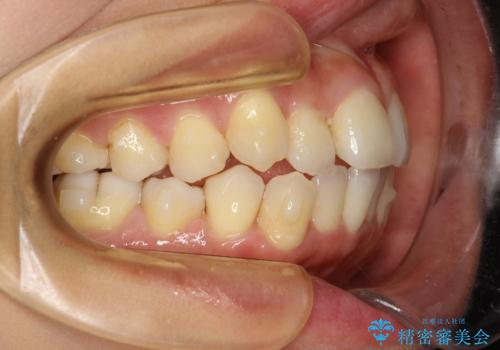

前歯が前後反対にかんでいる インビザラインによる目立たない矯正

- 前歯のかみ合わせを主訴に来院されました。

なるべく目立たずに矯正をしたいとのことで、インビザラインで矯正をすることとしました。

歯と歯の間をわずかに削り、ガタガタを改善しました。

目立たずに矯正を終えることができて、喜んでいただけました。